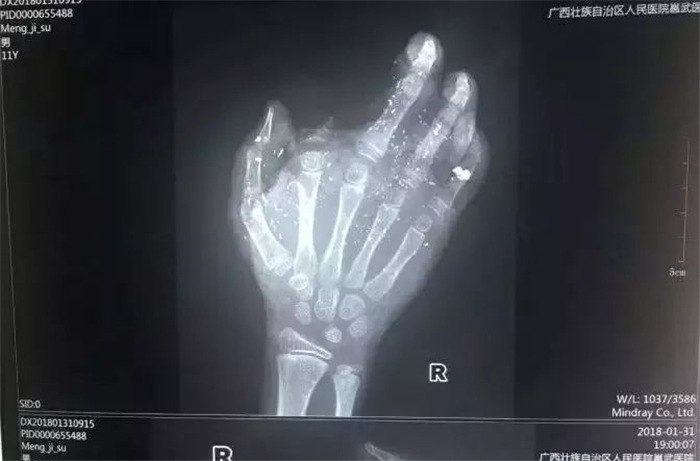

手机爆炸致男孩手掌被炸伤

2018年1月31日,广西发生一起手机爆炸事件,一名年仅12岁的小男孩手掌被炸得血肉模糊,右手食指被炸没了,拇指、中指、无名指也都炸伤,失去了供血,手掌皮肤被炸得稀烂。经CT检查,右眼内有2块手机碎片。据了解,手机之前出现过充电时发热现象,但家长当时未在意。